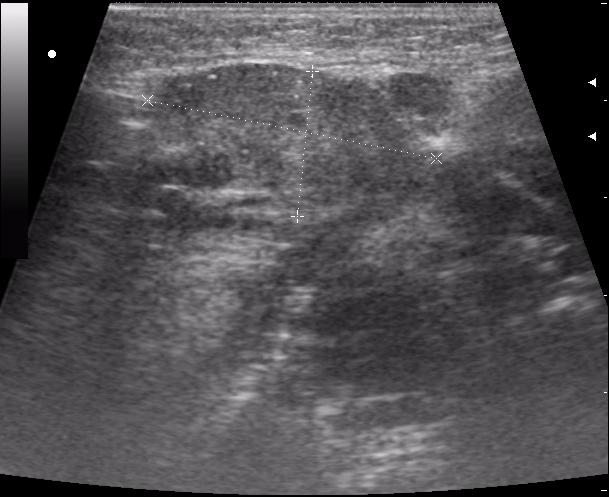

В гнойную хирургию положили ребенка с двусторонним шейным лимфаденитом в ст. инфильтрации.

мне этот лимфаденит показался совсем не лимфаденитным.

Да уж,явное увеличение околоушных желез.Да и реакция л.узлов значительная.Интресно понаблюдать в динамике.Слишком большие подчелюстные узлы.Спасибо за случай.